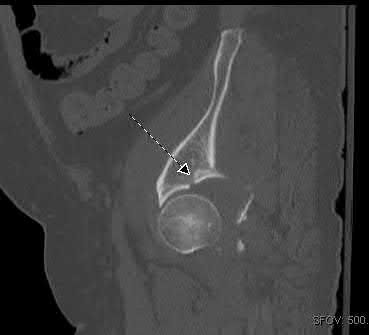

A 27 year-old patient sustains a fracture-dislocation of the acetabulum. Pelvic radiographs (Figures A and B) are taken at initial presentation and a CT scan (Figures C and D) is performed after reduction of the hip in the emergency room. What is the importance of the finding highlighted in the CT scan cuts?

The CT images shown in Figures C and D display significant marginal impaction of the joint surface.

Marginal impaction is common in posterior wall fractures and fracture-dislocations. Critical review of CT imaging of posterior wall fractures can help with preoperative planning for identifying impaction of the articular surface of the acetabulum. Restoration of the sphericity of the acetabulum to match that of the femoral head is important for successful outcome following ORIF of posterior wall fractures. A common surgical technique to accomplish joint surface restoration includes freeing the impacted articular segments, bone grafting of the void created to support the articular segments, and buttress plating of the posterior wall fracture fragments.

Figures A and B are radiographs of the posterior wall fracture and hip dislocation. They do not show the large amount of marginal impaction of the acetabular surface. Figure C (coronal reconstruction) and Figure D (sagittal reconstruction) point out a large a amount of marginal impaction of the acetabular. Note the disruption of the joint surface on the intact portion of the acetabulum.